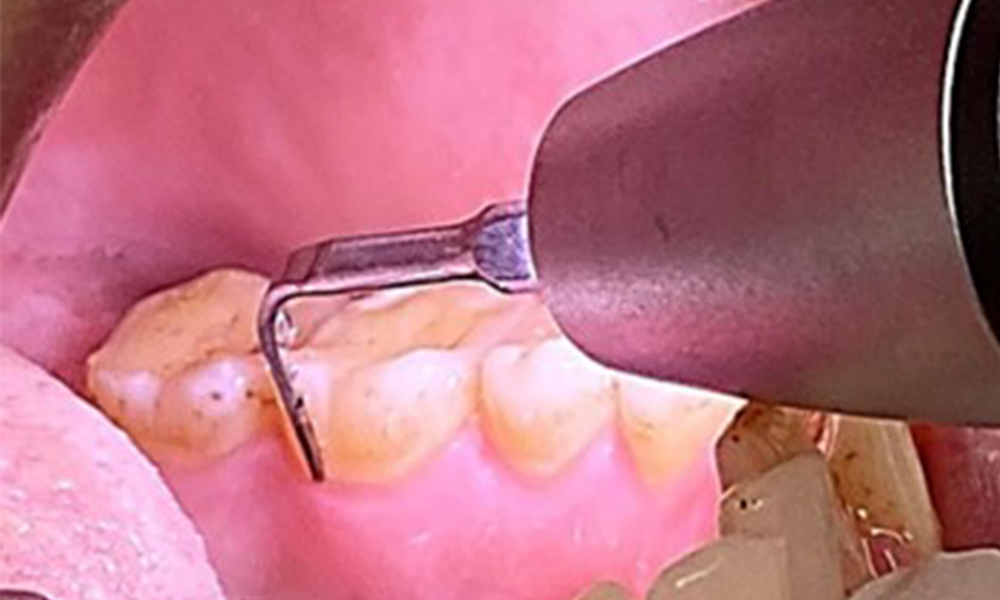

Obiectivul planului trebuie sp fie controlul riscului de boală, prin îndepărtarea biofilmului sub- și supragingival. Instrumentarul va fi ales în funcție de particularitățile pacientului. În primul rând, tartrul și eventualele concrețiuni vor fi înlăturate cu ajutorul pieselor cu ultrasunete și/sau manuale (Fig. 10).